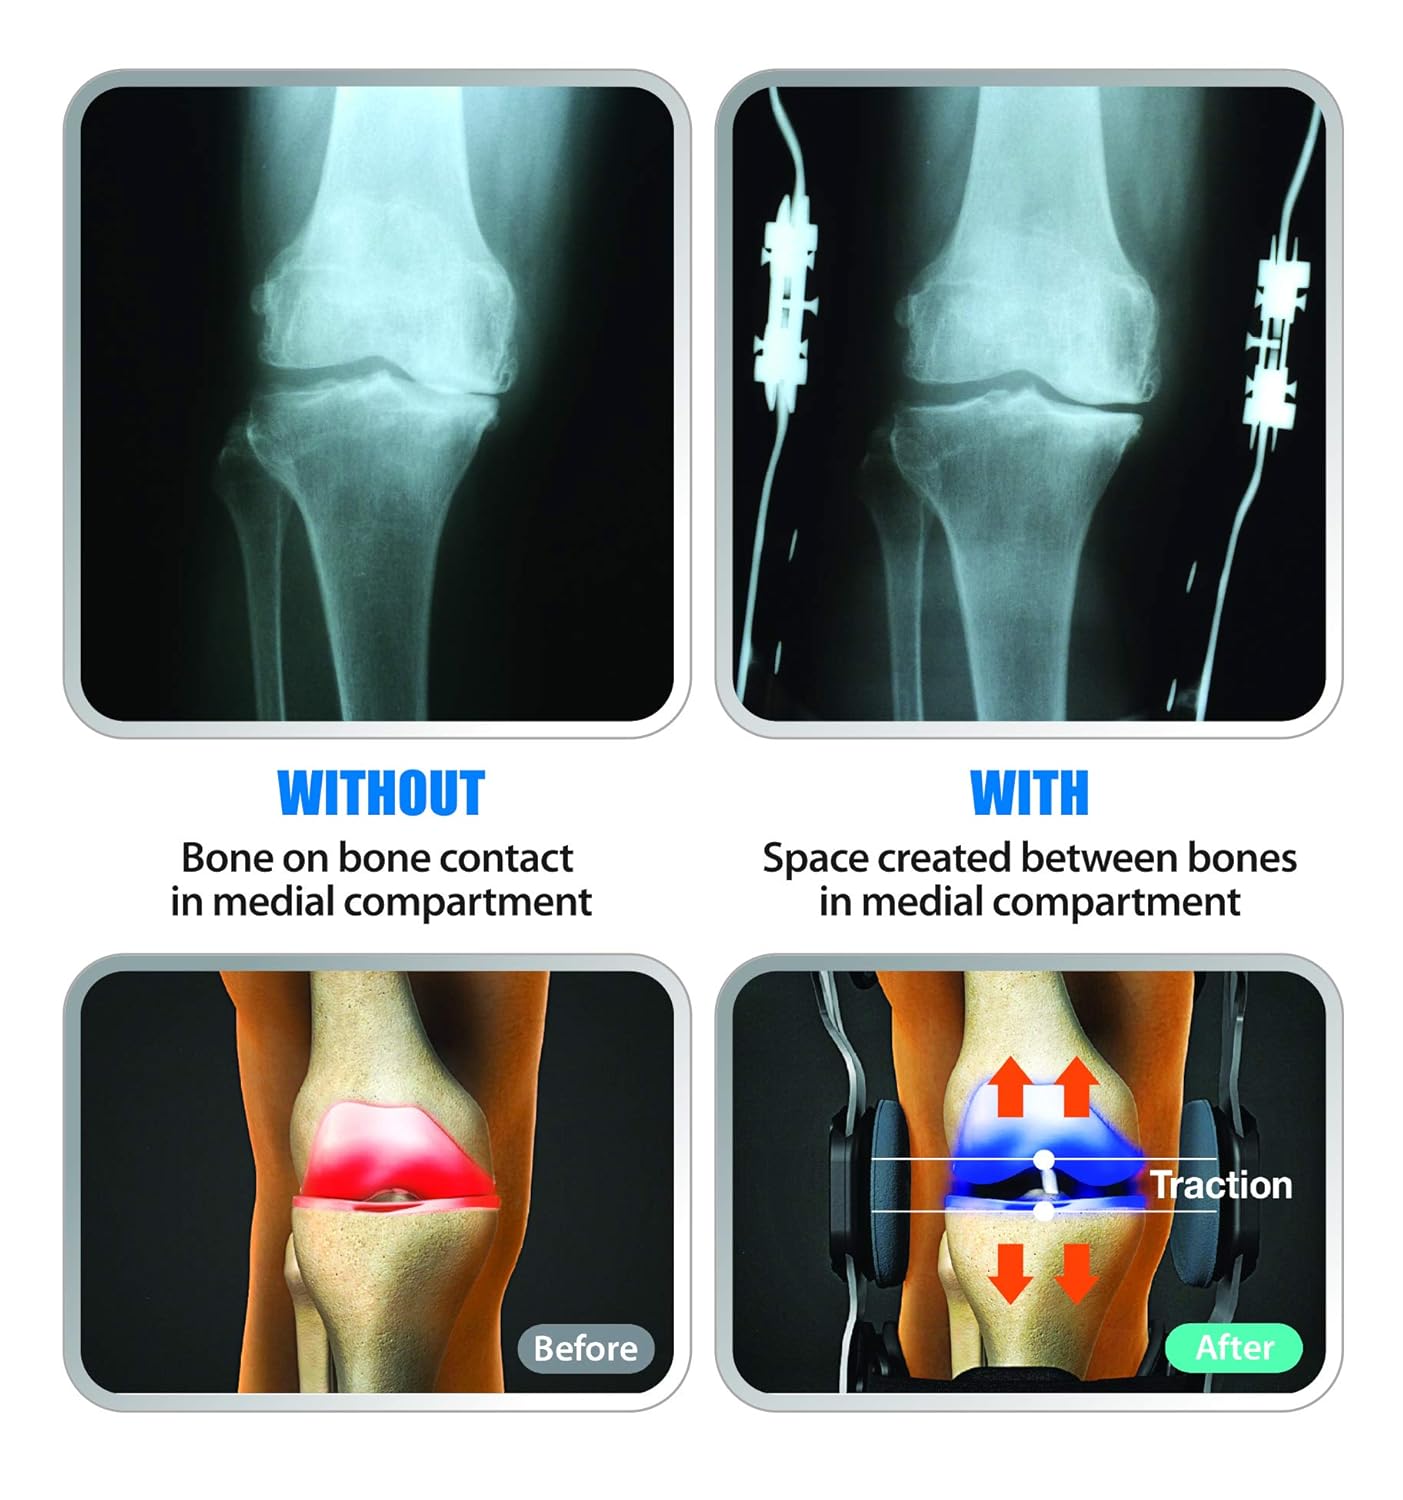

The posterior straps anchors on top of the calf and to the bottom of the hamstring. As the leg extends, the LTS Hinge gently pulls in the opposite directions, decompresses, and unloads the knee joint. This reduction of pressure supports and stabilizes the knee; eases pain and increases mobility. The LTS technology provides decompression to the knee joint by re-establishing the natural space and cushioning that’s missing between the femur and the tibia when afflicted with osteoarthritis.

How the DDS OA Pro Works